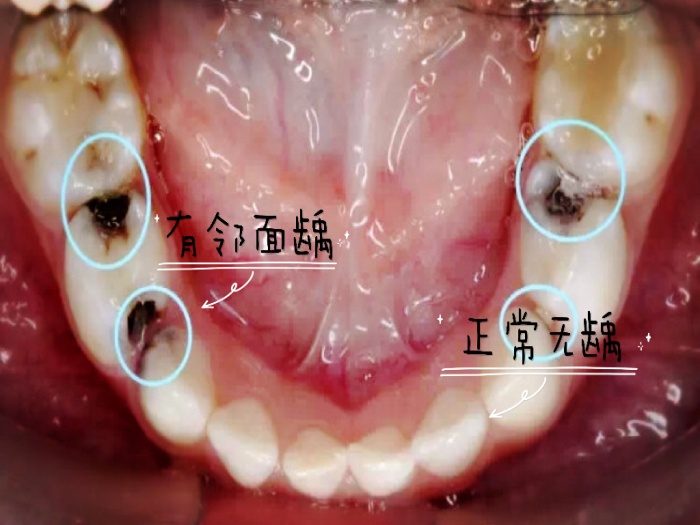

邻面的龋齿破坏了正常的牙齿结构,造成了缝隙的出现。相邻的两颗大牙邻面有龋洞,吃的东西就全塞进去了。有时候不一定能发现它,它却能每天都折磨你。想要解决的话,不要忘尽快去医院充填上。有些牙缝龋齿还不容易补,若补牙的材料跟旁边的那颗牙之间接触不紧密,或接触的部位不好,就会导致塞牙,非常常见。当然每个人牙齿情况不一样,具体怎么治疗还需要听专业医生的方案哦。

智齿在作怪。智齿是最容易塞的一颗牙了,因为大多数人智齿长得都不正,别的牙都是从下往上竖着长,可智齿经常从后往前横着长,于是它跟前面的牙之间就出现了一道楔形的沟,这样就极其容易塞牙。